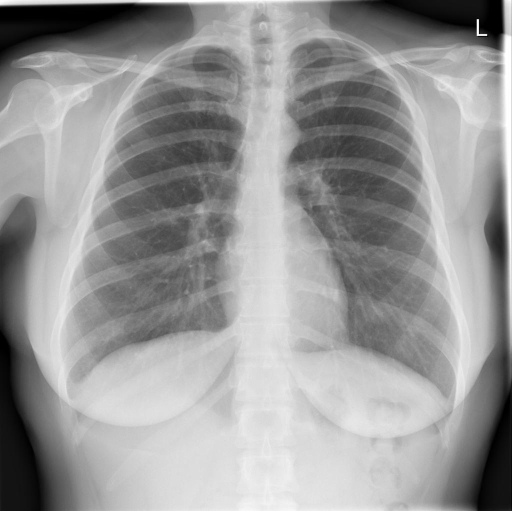

We compare our projected X-Rays with samples from the OpenI dataset for frontal and lateral views in Figure 5. The differences in the frontal view are due to the different positioning of the shoulder girdle. In the X-Rays, the arms are usually placed alongside the body, while in the projected images, the arms are raised due to the nature of the CT scan. In the lateral view, the X-Rays show a more comprehensive range of orientation and pose. However, the projected images, typically taken while the patient is lying down, result in similar poses between the different images. This leads to visual differences between images of female patients in both frontal and lateral views, such as the third column and second row of real X-Ray images and the first column and second row of projected images.